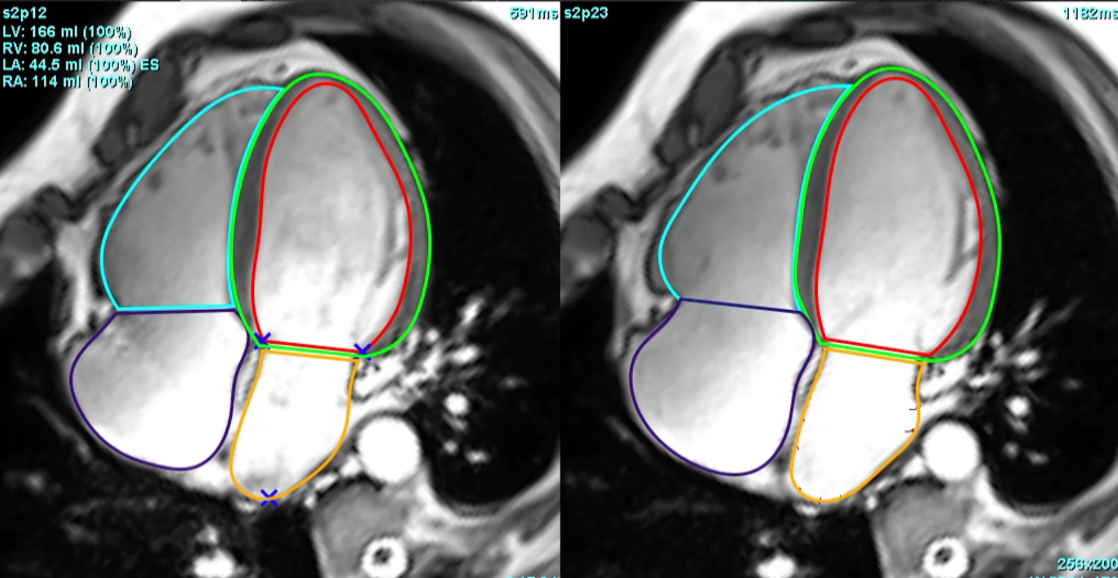

Left atrial dysfunction